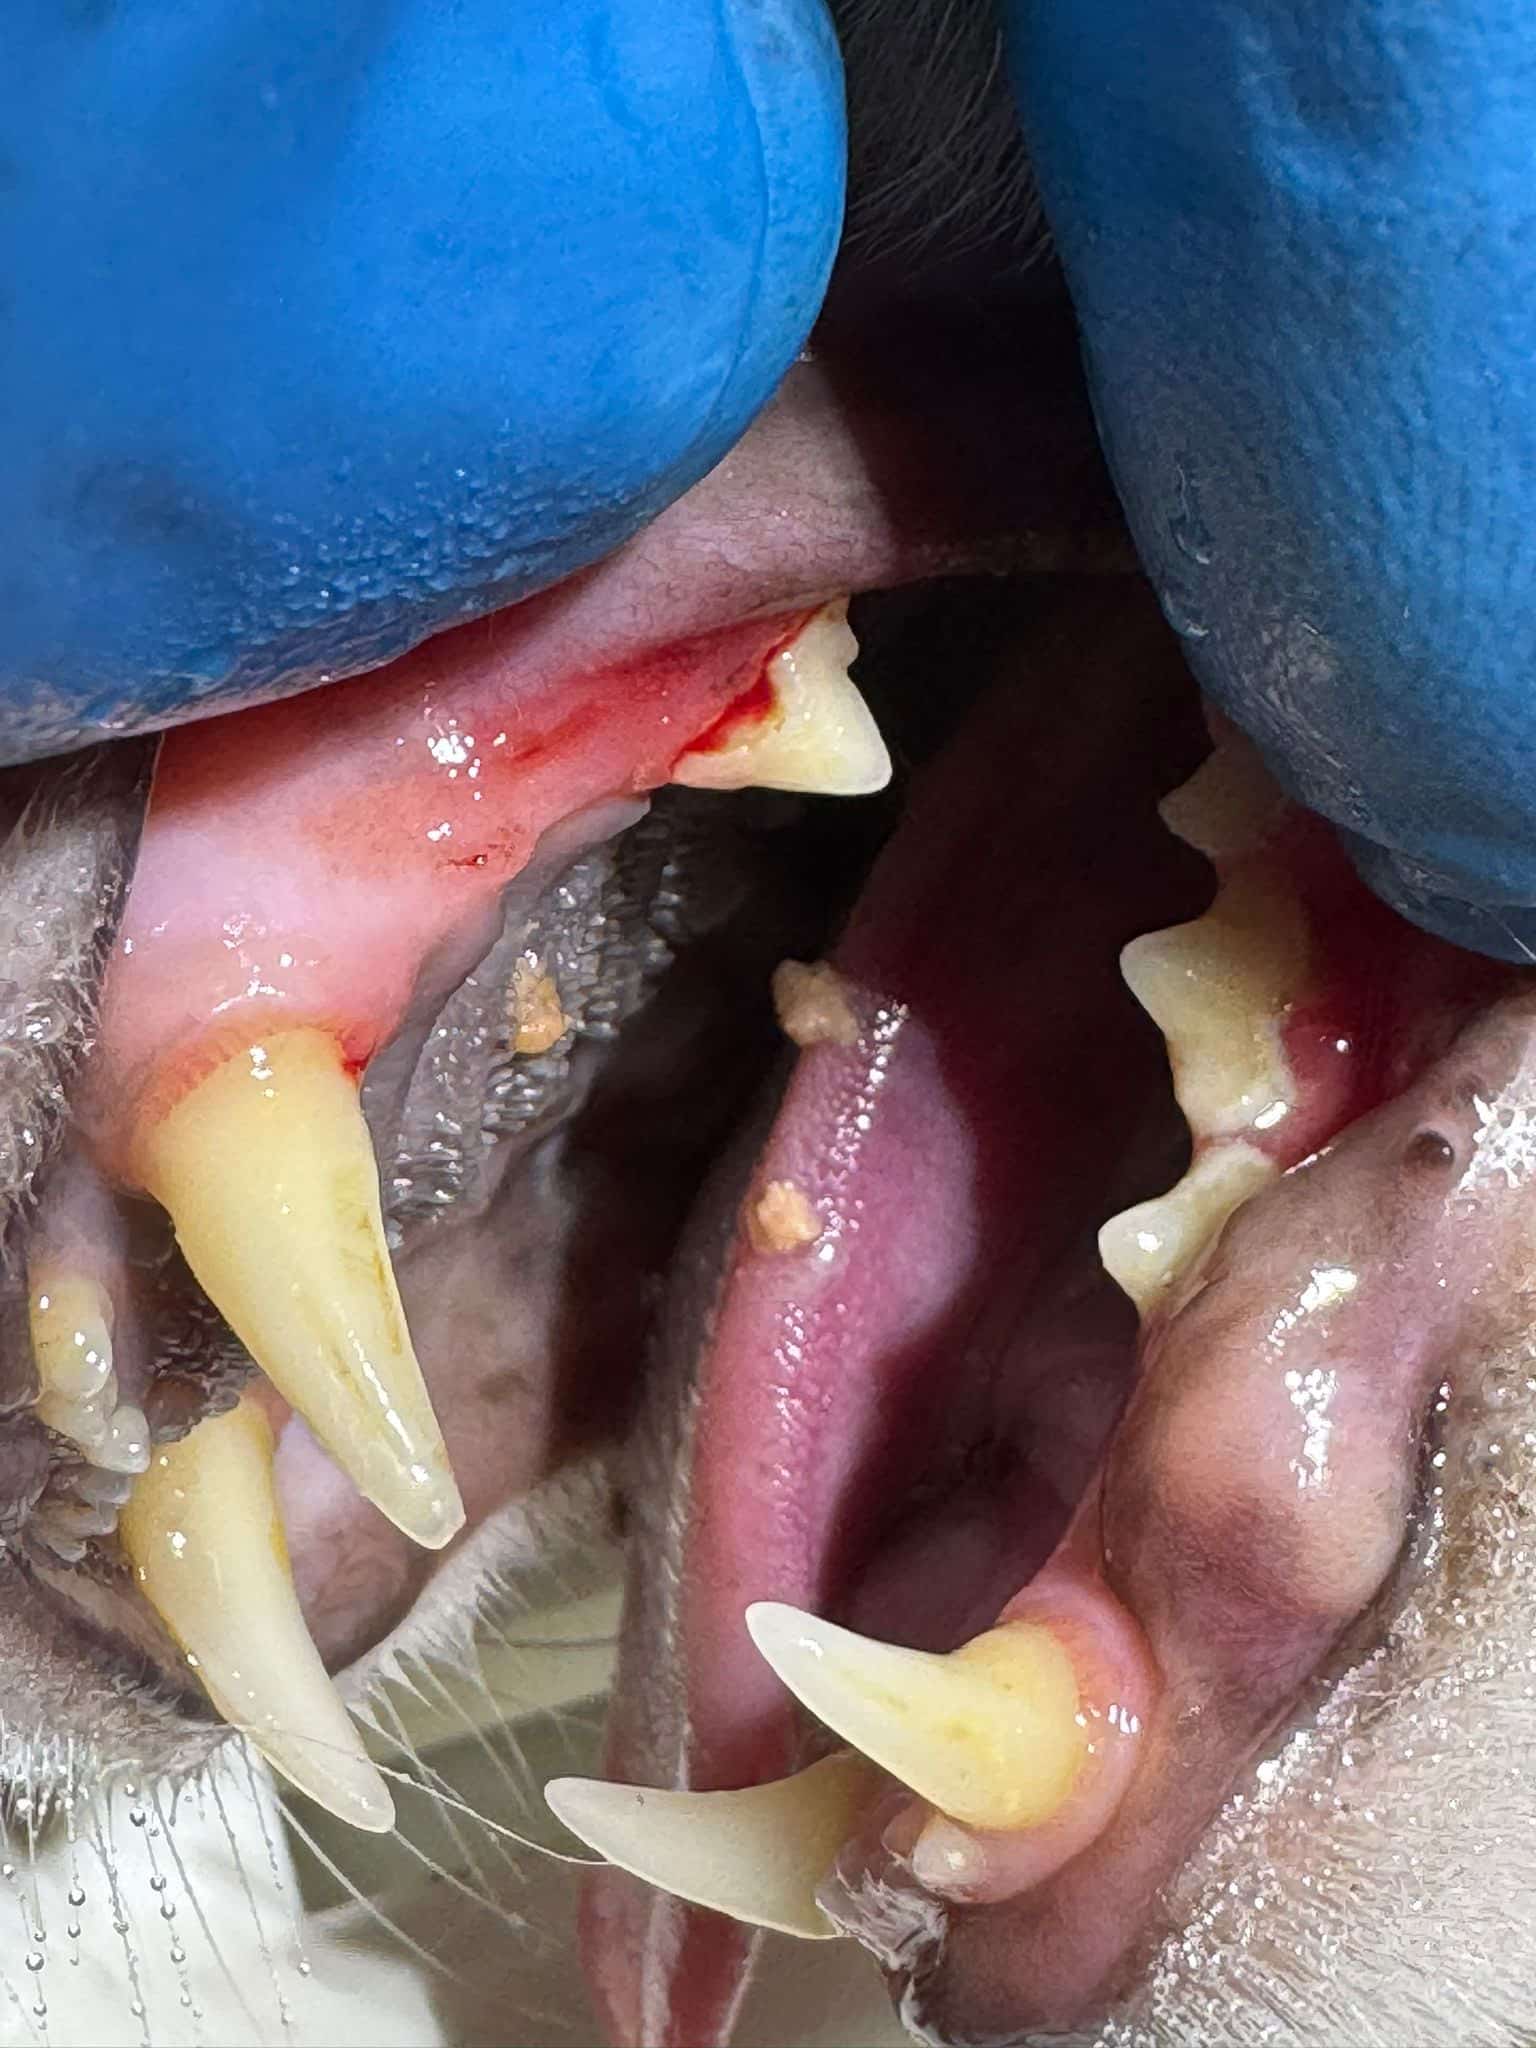

Beispielbilder vorher - nachher

Vorher

Nachher